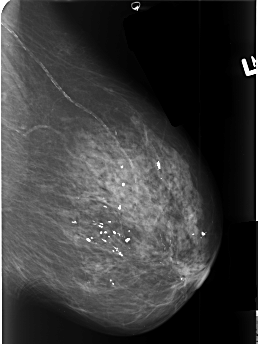

B_3411_1.LEFT_CC

LEFT_CC LINES 4488 PIXELS_PER_LINE 3184 BITS_PER_PIXEL 12 RESOLUTION 50 NON_OVERLAY